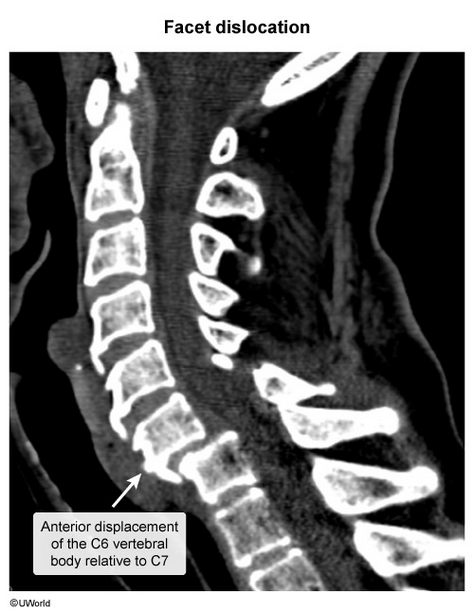

fell down stairs, weakness of elbow extension & wrist flexion

decreased pain sensation in index & middle fingers

typically occurs with forced flexion of cervical spine (ie, falling onto flexed neck) → single facet disloicated, radiculopathy

this case is c7 radiculopathy